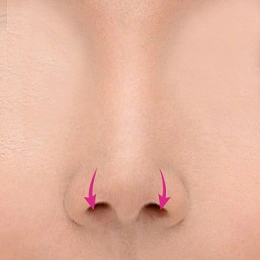

بینی رو به بالا یا بینی کوتاه به بینی ای اطلاق می شود که نسبت به صورت شخص بسیار کوتاه است. و در نمای جلویی دارای سوراخ های بینی بیش از حد قابل مشاهده است. بینی کوتاه یکی از بزرگترین چالش های جراحی زیبایی بینی است. این نوع بدشکلی معمولاً هر 3 لایه بافت بینی (یعنی پوست، پوشش داخلی، حمایت از استخوان) را درگیر می کند. بینی های کوتاه هم مشکلات زیبایی و هم نقص عملکردی دارند. زمانی که رینوپلاستی بینی کوتاه به طور ماهرانه انجام شود، می تواند بهبود چشمگیری ایجاد کند.

بینی کوتاه کلاسیک به سمت بالا و حالت فرورفتگی دارد به طور خاص، به عنوان بینی بدون ابعاد از زاویه نازو فرونتال تا نوک تعریف می شود. فقدان برآمدگی نوک اغلب در تشخیص وجود دارد. برای تعیین اینکه آیا بینی کوتاه وجود دارد، جراح ابتدا باید از ابعاد بینی طبیعی آگاه باشد. هنگام شناسایی بینی کوتاه، تجزیه و تحلیل تمام صورت، به ویژه نیمرخ، همراه با آنالیز به ویژه بینی انجام می شود.

حالت بینی زاویه دار رو به بالا

پوست و بافت های نرم نوک بینی با زاویه رو به بالا برداشته می شوند، سپس نوک بینی بعد از اینکه به سمت پایین کشیده شود ثابت می شود و غضروف اصلاح می شود تا بلند به نظر برسد.

حالتی که فقط سوراخ های بینی رو به بالا است

اگر فقط سوراخ های بینی به سمت بالا باشد، نوک بینی با در نظر گرفتن زاویه نازولبیال پایین می آید و اصلاح می شود. این کمک می کند تا چهره کلی را به جلوه پیچیده ای تبدیل کنید.